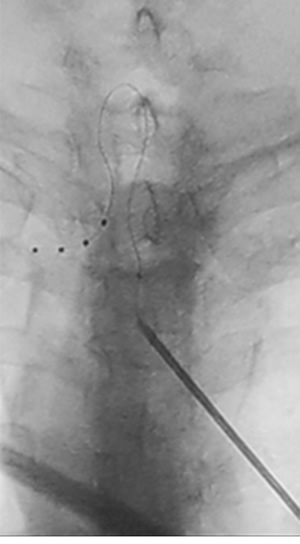

Metodología: Se presentan los resultados de un estudio observacional, prospectivo, en 10 pacientes a los que les ha sido implantado el sistema de estimulación del ganglio de la raíz dorsal (EGRD), según la práctica clínica habitual, para el alivio de dolores neuropáticos refractarios al tratamiento médico e intervencionista. Los objetivos principales del estudio fueron la valoración en los cambios de la intensidad del dolor, en la funcionalidad y en los niveles de ansiedad y depresión. El tiempo de seguimiento fue de 6 meses tras el implante del generador.

Resultados: 8 pacientes superaron la fase de prueba al constatarse una disminución de la intensidad del dolor superior al 50 %: 5 de estos sufrían dolores secundarios a lesión nerviosa periférica traumática o postquirúrgica, los otros 3 padecían dolores neuropáticos de otros orígenes. Se constató una disminución de la intensidad del dolor del 63 % en la EVA, mejoría general subjetiva del 70 %, disminución de la toma de analgésicos, mejoría funcional en la escala Oswestry, así como en los niveles de ansiedad y depresión (Escala HAD). Los mejores resultados se obtuvieron en los pacientes en los que se les implantó un electrodo en el ganglio de la raíz dorsal L5 para el tratamiento de dolores en miembros inferiores y con sensación de alodinia. No se objetivaron cambios en la estimulación en relación con la postura y sí gran concordancia entre el área de parestesia y del dolor. Las complicaciones fueron escasas y en ningún caso graves.

Results: Eight patients passed the test phase when a decrease in pain intensity was found to be greater than 50 %, 5 of these suffered pains secondary to traumatic or postsurgical peripheral nerve injury, the other three fallisuffered neuropathic pains of other origins. We found a 63 % decrease in pain intensity in the VAS, a 70 % subjective general improvement, a clear decrease in analgesia, a functional improvement on the Oswestry scale, and an improvement in anxiety and depression levels (HAD scale). The best results were obtained in patients with electrode implanted at L5 root for the treatment of pain in the foot or ankle and allodynia. We found an absence of changes in stimulation in relation to posture and an area of stimulation similar with the area of pain. The complications were few and not severe.